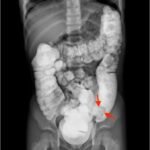

Intussusception is the telescoping of bowel into an adjacent segment of bowel and has an associated risk for bowel ischemia and perforation. The classic triad of abdominal pain, blood in stool, and an abdominal mass is present in less than 40% of pediatric cases and is less common in older children.1 Ultrasound has a high sensitivity and specificity for the diagnosis of intussusception, and once diagnosed, treatment modalities include reduction by either ultrasound or fluoroscopic guided air or hydrostatic enema. The risk of recurrence after successful reduction occurs in up to 12% of pediatric patients and occurs more frequently in older children and children with a pathologic lead point.2 We present a case of a 6-year-old child with colocolic intussusception that was successfully reduced and recurred within five days due to a large colonic polyp.